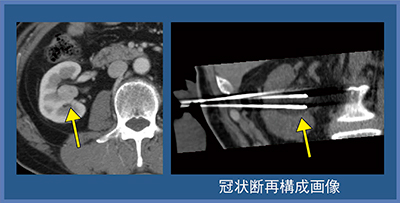

症例1(70歳代,男性)は,腎門部のclear cell RCCである。冠状断再構成画像で,3本のニードルとその周囲に黒くアイスボールが認められる(図2)。腫瘍が黒い範囲に入ったことを確認して治療を終了した。経過観察では,黒く描出された腫瘍部が徐々に吸収され,最終的には同定できなくなった(図3)。

図2 症例1:腎門部clear cell RCC(70歳代,男性)

図3 症例1:治療後経過